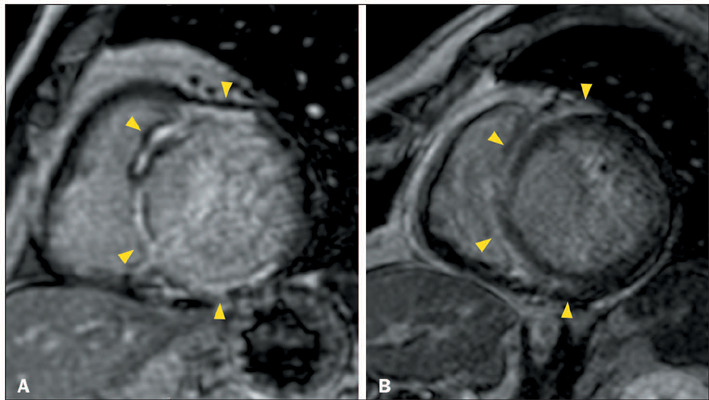

Advances in cardiac magnetic resonance have promoted tissue characterization with high spatial and contrast resolution, and late gadolinium enhancement (LGE) sequences have improved the detection of myocardial fibrosis. The distribution pattern of LGE facilitates differentiation between ischemic and nonischemic etiologies and aids in refining diagnoses within nonischemic cardiomyopathies, suggesting specific etiological factors. A distinctive nonischemic LGE pattern that has recently gained prominence is the ring-like pattern, defined as a subepicardial or mid-wall circumferential or semi-circumferential enhancement, which involves at least three contiguous segments within the same short-axis slice. Initially identified as a diagnostic marker for desmoplakin and filamin C-related cardiomyopathies, the pattern has been reported in nongenetic conditions; nevertheless, it remains an uncommon finding in these diseases. In this article, we aim to present the differential diagnoses of ring-like LGE and its mimics. The combination of epidemiological, clinical, electrocardiographic, and additional features enables a focused refinement of the differential diagnosis associated with ring-like LGE.

Abstract Image